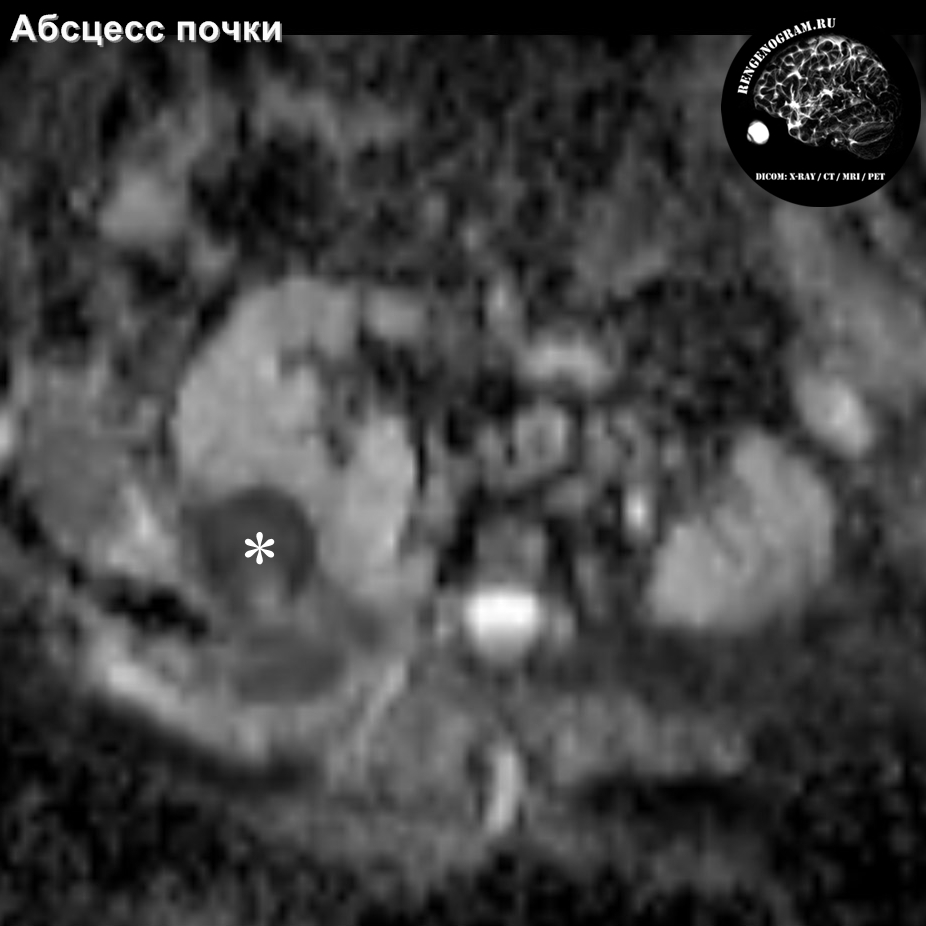

КТ диагностика тубоовариального абсцесса: Подходы и изображения

Раздел: Объективный взгляд